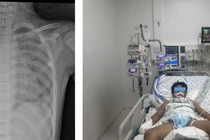

Nỗ lực cứu trẻ 10 tuổi đuối nước ngay tại hồ bơi

Phụ huynh không được chủ quan khi cho trẻ đi bơi, kể cả tại hồ bơi có nhân viên cứu hộ. Trẻ luôn cần có người lớn quan sát liên tục.